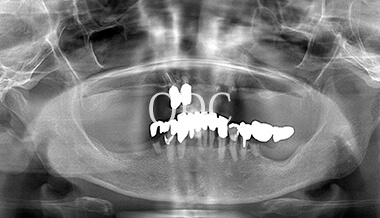

パノラマX線写真

術 前

術 後

術前・術後のパノラマX線写真です。上顎(オールオン4)は4本のインプラントにチタンフレームの上部構造が固定されているのがおわかりになると思います。下顎のインプラント埋入部位、上顎のインプラントの本数、再度写真をご覧いただくと、とてもインプラントが埋入されているとわからない程の外観、下顎の残存歯(元々の自分の歯)とも区別がつかない審美性が実現されています。